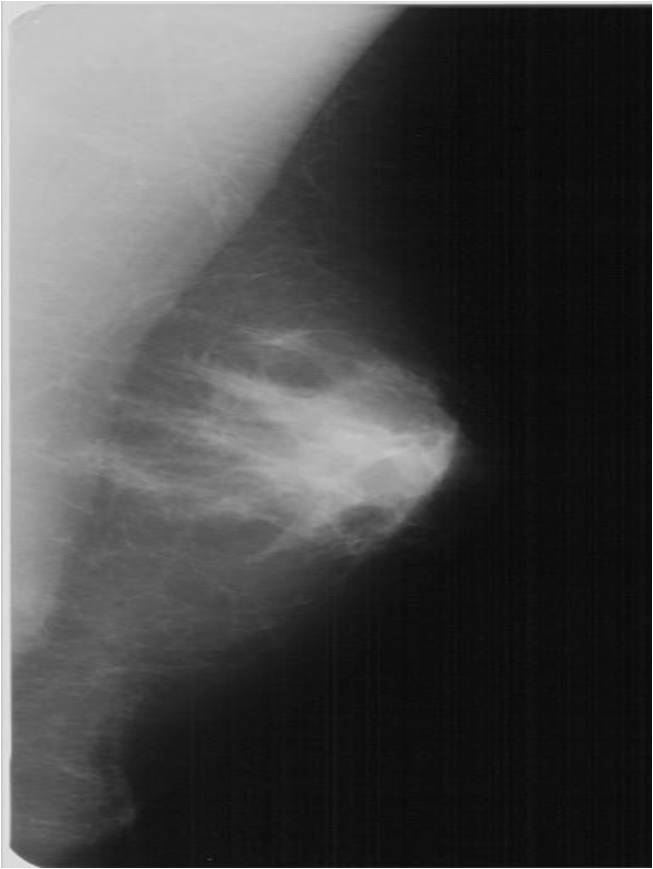

Pathologic lesions in the breast appear as various shapes and densities of soft tissues or calcificications or as the combinations of these two on mammography (Picture 16.). At many times only a few scattered, ill-defined, pleiomorphic microcalcifications indicate the presence of a pathologic lesion.

The soft-tissue lesions can appear as well-defined, rounded or oval shaped (Pictures 13.,14.) or as ill-defined, star-shaped masses (Picture 15.). Rounded or oval lesions are in most cases benign and their malignant proliferation is rare, they do not require surgical removal. These lesions are usually cysts and fibroadenomas, at other times hamartomas, lipomas and at very few times malignant tumors.

Star-shaped lesions are very typical of malignant tumors.

o “White star”: describes the tumor body with dense spiculations of various lengths appearing around the core = carcinoma

o “Black star”: there is no tumor body, the central part is transparent. The spiculations are arched, long and thin. These usually do not indicate the entity of the lesion; they can either be benign or malignant. Examples are lobular carcinoma, post-radiation scar tissue, fatty necrosis or postoperative scar tissue (patient history is indicative!).